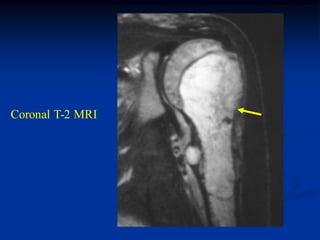

CLASSIC      Case #159

21 year male with angiosarcoma pelvis

Coronal T-1 MRI

tumor

Axial T-1 MRI